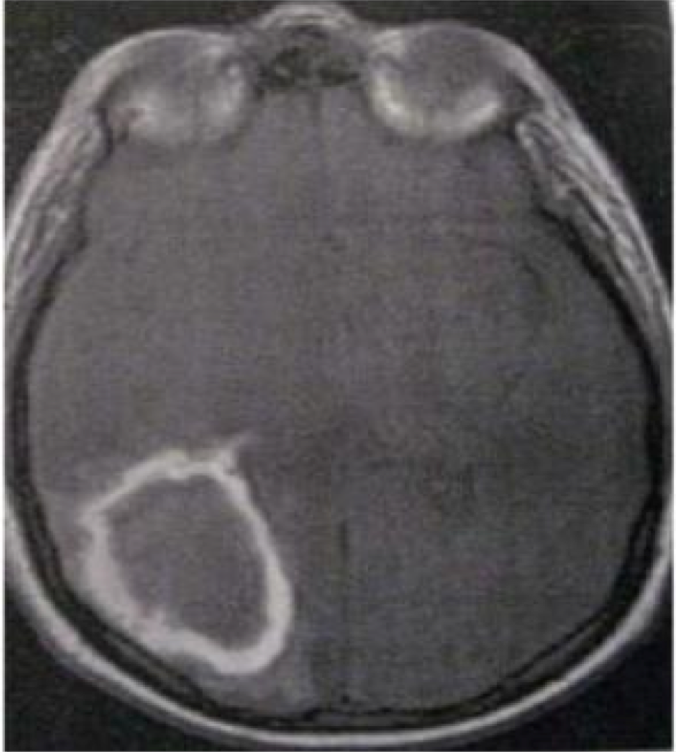

seorang perempuan usia 42 tahun dibawa ke bagian gawat darurat dalam keadaan berkunang-kunang dan citra MRI T2-weighted sebagaimana yang ditunjukkan pada gambar di bawah ini. diagnosis manakah yang paling mungkin?

A. Ganglioma lobe Temporal

B. Tumor neuroepiteliel disembrioplastis

C. Kista epidermoid

D. Aneurisma

E. Neurokistiserkosis

D